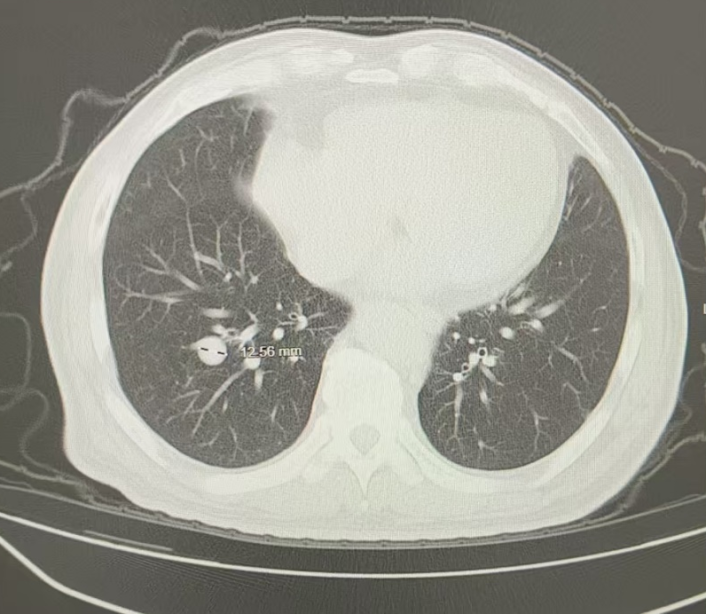

图1 患者基线胸部影像学图像(2024年4月16日)

ECT骨扫描未见骨转移;B超提示未见肝转移灶;头颅MRI提示未见脑转移